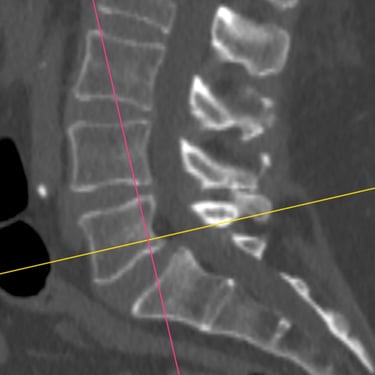

La listesis lumbar L5–S1 es una afección en la que una vértebra se desliza sobre otra, provocando inestabilidad, dolor lumbar y, en muchos casos, compresión de las raíces nerviosas. Cuando el tratamiento conservador no logra controlar los síntomas, la fusión intersomática transforaminal (TLIF) se presenta como una opción quirúrgica efectiva. Este procedimiento permite descomprimir las estructuras nerviosas, restaurar la alineación vertebral y lograr una fijación sólida mediante tornillos transpediculares e injerto óseo. La técnica TLIF reduce el dolor, mejora la estabilidad de la columna y favorece una recuperación funcional progresiva y segura.